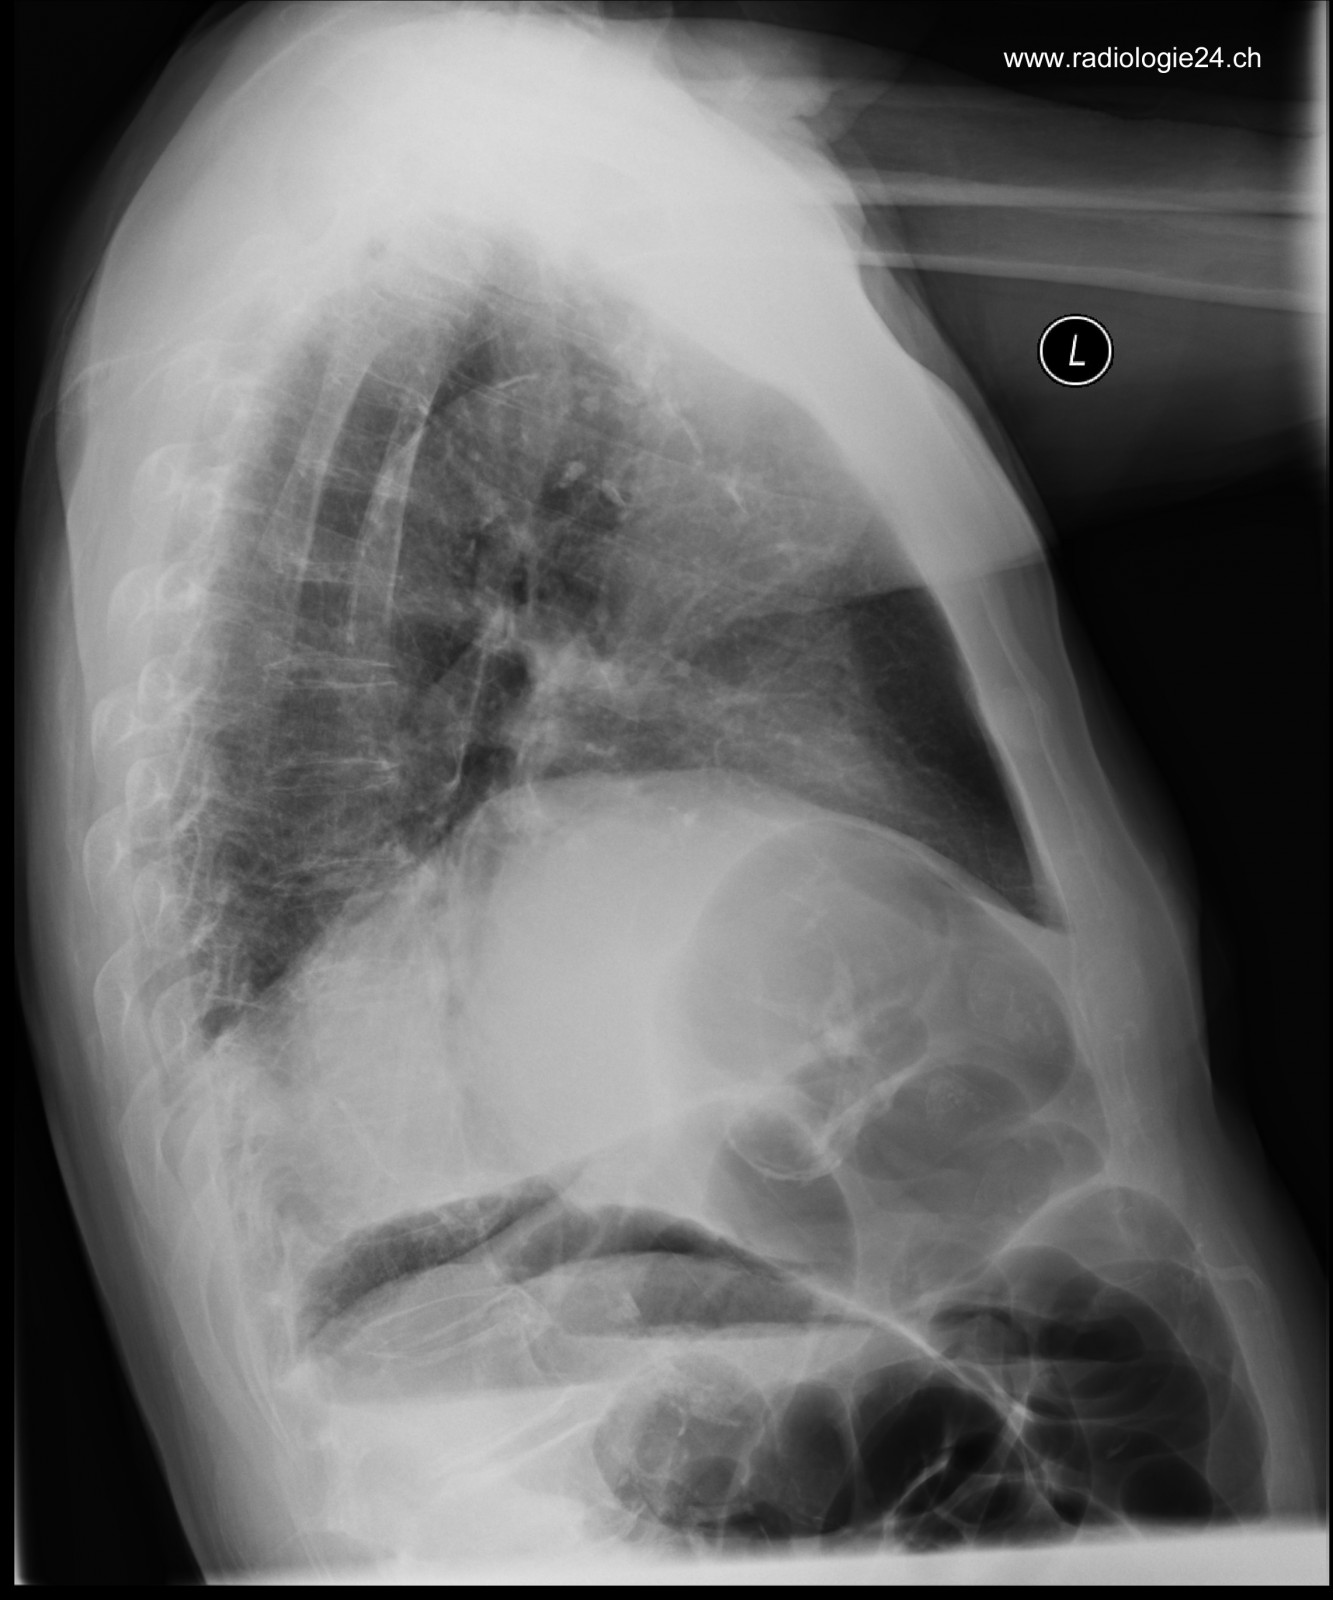

Röntgenfall des Monats Juli 2017 mit Auflösung

78 jähriger Patient mit zunehmender Dyspnoe und Thoraxschmerzen

seitlich

Bild vergrössern